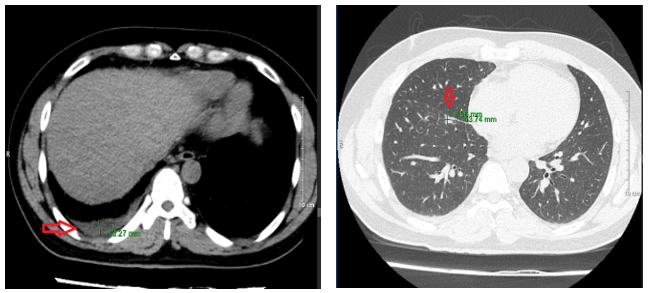

- Chụp cắt lớp vi tính ổ bụng: Hình ảnh theo dõi u máu gan phải kích thước 18x20mm

- Chụp cộng hưởng từ sọ não: Hiện tại không có bất thường

-        Chụp cắt lớp vi tính lồng ngực sau điều trị 10 tháng:  Nhu mô thùy trên sát rãnh liên thùy lớn có tổn thương dạng hang chứa khí kích thước 18x13mm, thành dày, có xơ hóa lân cận. Nhu mô phổi còn lại có vài nốt đặc, nốt lớn nhất đường kính 6mm. Phổi trái có vài nốt đặc bờ đều đường kính 5 mm.

Hình 4: Hình ảnh chụp cắt lớp vi tính lồng ngực sau điều trị 10 tháng: các nốt tổn thương gần hết và không có tràn dịch màng phổi

-        Chụp cắt lớp vi tính ổ bụngNốt đặc xương thân -cánh trái xương cùng kích thước 15x8mm và xương cánh chậu trái kích thước 13x9mm. Hình ảnh theo dõi u máu gan phải/ gan nhiễm mỡ

Hình 5: hình ảnh chụp cắt lớp vi tính ổ bụng sau điều trị 10 tháng không có tổn thương nghi ngờ thứ phát